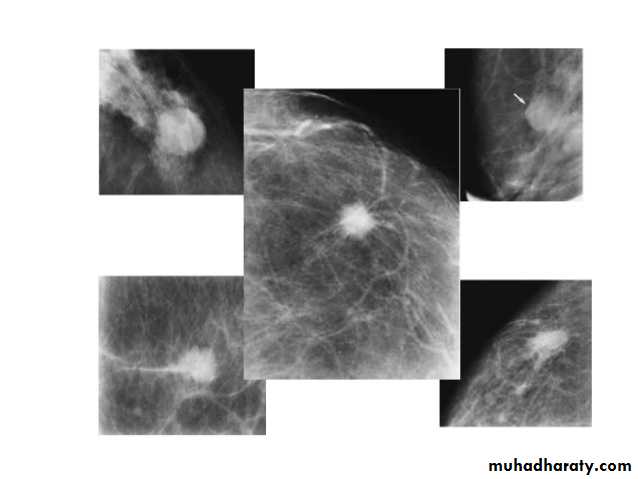

Breast density & who can U detect a mass lesion

Your mammogram report must take in consideration & assessment the breast density. Breast density is based on how fibrous and glandular tissue tissues are distributed in your breast, vs. how much of your breast is made up fatty tissue.

Dense breasts are not abnormal, but they are linked to a higher risk of breast cancer. We know that dense breast tissue can make it harder to find cancers on a mammogram. Still experts do not agree what other tests, if any, should be done in addition to mammograms in women with dense breasts who aren’t in a high-risk group (based on gene mutations, breast cancer in the family, or other factors